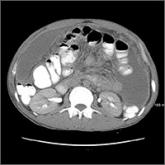

ArticleImmigrant with stomach pain, distension, nausea, and fever • Dx?Author:Callie Waller, DOPublish date: August 31, 2017► Abdominal pain and distension► Nausea► Declining appetiteRead More